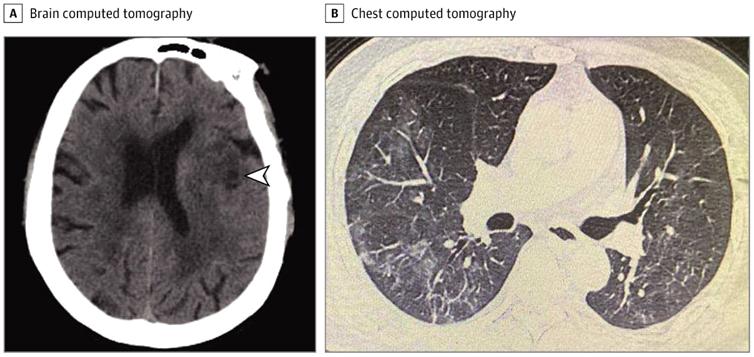

Fig 1

Fig 2

Fig 3